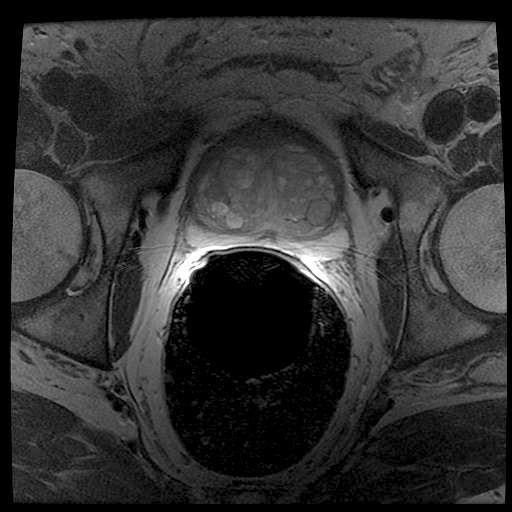

IV-A Image Data: Synthetic TRUS Images

It is a considerable challenge to validate any approach to computed consensus contouring. The ultimate test, to be sure, is to measure the accuracy of the computed consensus contour 𝐂𝐂\mathbf{C}. However, this depends on assessing the quality of the consensus. Unless there is a “gold-standard segment” G𝐺G for each image, reliable validation will not be straightforward, and any particular observation will be inconclusive. Of course, this is not feasible with real images, for which there is no gold standard. Hence, we generated synthetic images whose gold segments were known a priori. For this reason, we used synthetic images that simulate transrectal ultrasound (TRUS) images.

TRUS images of prostates may be used to both diagnose and treat prostate diseases such as cancer. Starting with a set of prostate shapes P1,P2,,Pmsubscript𝑃1subscript𝑃2subscript𝑃𝑚P_{1},P_{2},\dots,P_{m}, we created random segments Gisubscript𝐺𝑖G_{i} through combinations of those priors, adding noise along with random translations and rotations, and we distorted the results with speckle noise and shadow patterns. Each image Iisubscript𝐼𝑖I_{i} is thus created from its gold Gisubscript𝐺𝑖G_{i}. Consequently, we can simulate k𝑘k user delineations Si1,Si2,,Siksuperscriptsubscript𝑆𝑖1superscriptsubscript𝑆𝑖2superscriptsubscript𝑆𝑖𝑘S_{i}^{1},S_{i}^{2},\dots,S_{i}^{k} by manipulating Gisubscript𝐺𝑖G_{i} via scaling, rotation, and morphological changes, and we can simulate edits by running active contours with variable user-simulating parameters. The variability of user delineations was simulated according to several factors: error probability ([0,0.05]00.05[0,0.05]), anatomical difficulty (=0.2absent0.2=0.2 out of [0,1]01[0,1]), and the scaling factor for morphology (form 1×1111\!\times\!1 to 21×21212121\!\times\!21). The user was modelled according to the level of experience (a random number from (0,1]01(0,1]), the user’s attention (a random number from [0,1]01[0,1]), and the user’s tendencies in terms of the segment size (a random number from [1,1]11[-1,1]), whether tending to draw contours that are relatively small (1absent1\rightarrow\!-1) or large (+1absent1\rightarrow\!+1).

We generated 500 images from their corresponding gold-standard images. Furthermore, we generated 20 different segments for each image, assuming that there were 20 users. Figure 4 shows three examples of real and synthetic TRUS images. One should bear in mind that the purpose here was not to simulate the images realistically, but rather to have a base from which to generate variable segments from a perfect segment. Figure 5 shows an example of the gold segments and simulated user contours. The variability, coupled with the gold segment, is what is needed to validate our approach.

Figure 4: Sample TRUS (top) and simulated images (bottom).